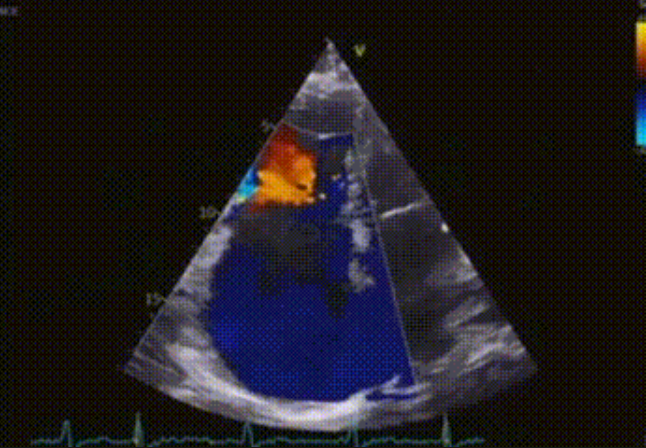

術前心臟超聲提示:極重度三尖瓣返流,右房容積明顯增大,三尖瓣瓣環(huán)顯著擴張。

術后心臟超聲提示:LuX-Valve Plus植入后,三尖瓣瓣環(huán)處可見人工瓣膜回聲,未見返流,人工瓣膜穩(wěn)定,瓣葉開閉良好,連續(xù)多普勒估測三尖瓣平均跨瓣壓差僅為1mmHg。